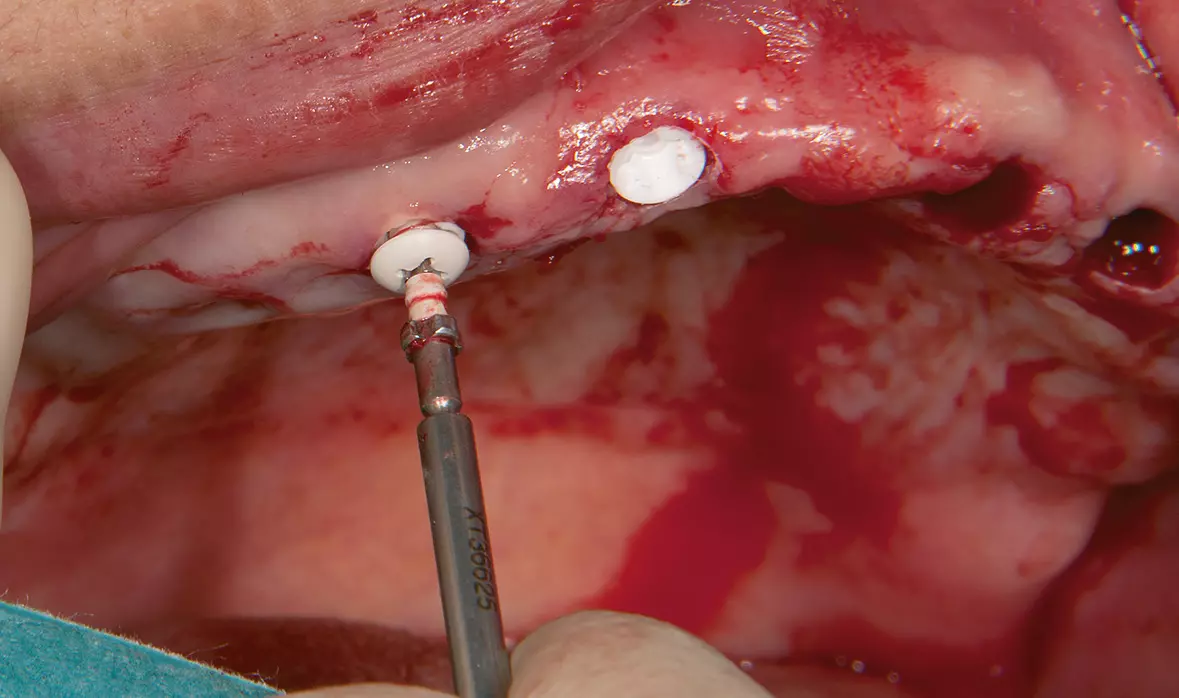

Abb. 42: Docklocs-Abutments mit Eindrehinstrument. Dr. Michael Leistner

Abb. 42: Docklocs-Abutments mit Eindrehinstrument.